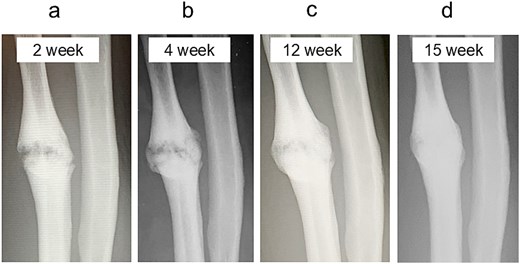

Radiographic findings during follow-up. (a) At 2 weeks, early callus formation is observed. (b) At 4 weeks, increased callus formation is noted. (c) At 12 weeks, near complete union is evident. (d) At 15 weeks, complete union achieved.

A 54-year-old man sustained a mid-diaphyseal ulnar fracture from a direct kick during karate practice. Initial conservative treatment at another hospital failed to achieve union over 12 months, and he was referred to our clinic with a diagnosis of nonunion. At presentation, he reported significant pain with a numerical rating scale (NRS) score of 6, and radiographs showed a 9 mm interfragmentary gap (Fig. 1a and b). Given his pain, we initiated proactive conservative management with prolotherapy, primarily targeting pain relief. Ultrasound revealed marked doppler signals at the nonunion site, suggesting inflammation and neovascularization. A mixture of 6 ml 50% dextrose and 4 ml 1% lidocaine (final 30% dextrose) was injected under ultrasound guidance into the neovascularized tissue and fracture gap (Fig. 2a and b). From the second session onward, bone healing had progressed to the point where the solution could no longer be injected between the bone fragments, so subsequent injections were administered around the periosteum. No restrictions were placed on weight-bearing or activity. Pain improved to NRS 4 at 2 weeks and to NRS 2 at 4 weeks, with early callus formation seen on radiographs. Prolotherapy was repeated five times at 2–3 week intervals. By 12 weeks, the patient was pain-free (NRS 0) and returned to karate. Radiographic union was confirmed at 15 weeks (Fig. 3a–d). Although initiated for pain control, prolotherapy led to relatively early bone union without surgery or complications.